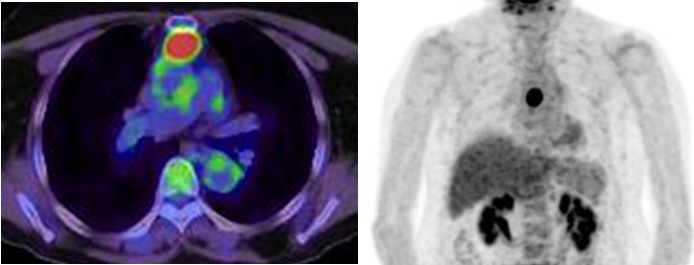

A 69-year-old woman visited our hospital complaining of neck discomfort. Computed tomography (CT) showed no abnormal shadows in the neck, but a 2.5 cm tumor was detected in the anterior mediastinum (Figure 1). Chest radiography did not reveal an abnormal shadow (Figure 2). Magnetic resonance imaging showed a low-signal intensity on T1-weighted images, iso-signal intensity on T2-weighted images, and a heterogenous pattern on gadolinium-enhanced images (Figure 3). Abnormal hyper uptake (maximum standardized uptake value [SUVmax] = 9.72) was found at the tumor on positron–emission tomography (Figure 4). The tumor was suspected to be an invasive thymoma or thymic carcinoma.

Figure 4: Positron–emission tomography. Abnormal hyper uptake (SUVmax = 9.72) was found at the tumor.